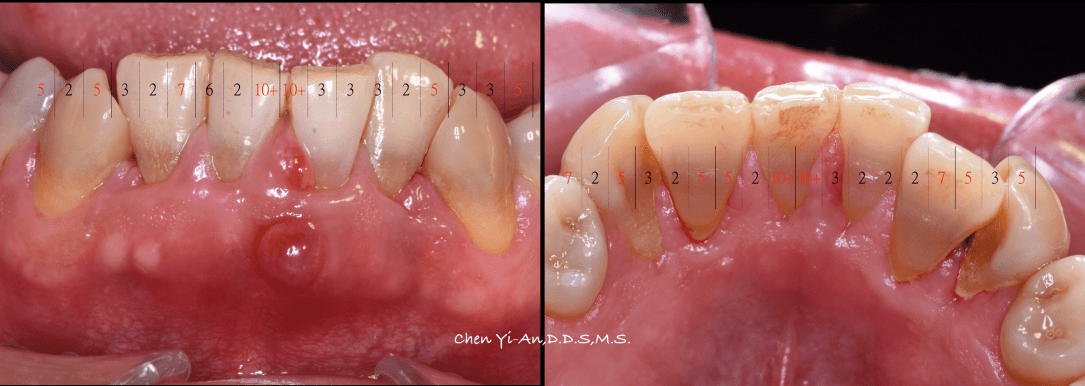

健康的牙齒跟牙齦幾乎是緊密貼合的。牙醫師會使用有刻度的牙周探針,針對每一顆牙齒進行探測檢查,沿著牙面弧度提放式行走,紀錄每一顆牙齒的牙周狀態。健康的牙周狀態,以探針探測,深度介於1-3mm之間,通常不會有滲血狀態出現,而是否有「探測時出血」,是牙齦健康的重要指標之一。當結石形成,發炎的現象越來越嚴重,患有牙周病的牙齒,探測深度會大於3mm,也就是進一步形成牙周囊袋,並且會逐漸加深。由於牙周病菌具有厭氧特性,氧氣較少的牙周囊袋正好成為孕育牙周病的溫床。牙周病菌不斷增生,散發出毒素,並且引發宿主免疫反應,造成齒槽骨吸收。當齒槽骨高度下降,便降低了對牙齒的支持力。如果置之不理、沒有妥善治療,經常導致牙齒喪失或需要拔除。

了解與牙周病的發展,也可幫助民眾做簡單的自我檢查,以便早期發現、早期治療。健康的牙齦組織為但淡粉紅色,牙齦結實。一旦牙菌斑累積,初期會引發牙齦炎,此時牙齦外觀紅腫,刷牙時牙齦會出血。當牙齦發炎沒有即時控制治療,牙齦炎將發展至牙周病,病患會發現牙齦明顯退縮、牙縫越來越大、牙齒開始對冷熱酸痛敏感、口臭、牙齒搖動,咀嚼時不如以往紮實有力,甚至會有疼痛感,嚴重者口內會出現化膿現象。